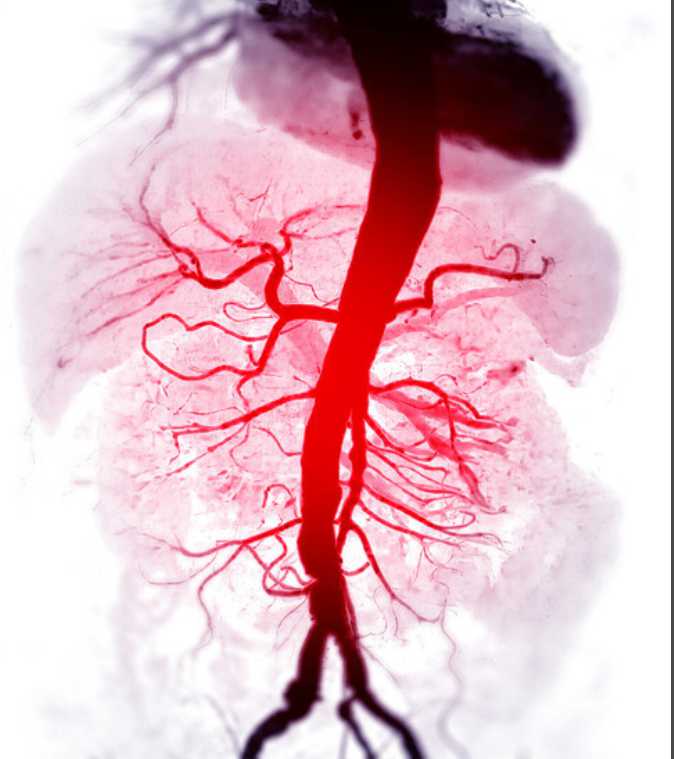

お腹の中で血管が膨らむ疾患「腹部大動脈瘤」は、適切な治療時期を逃し大動脈が破裂すると生命を脅かすため、高齢者など高危険群では定期的検診と早期治療、生活習慣の改善を通じた予防が重要だ=ゲッティイメージバンク(ハンギョレ新聞社)

お腹の中で血管が膨らむ疾患がある。それが「腹部大動脈瘤」だ。心臓から全身に血液を送る大きな血管である大動脈が弱くなり、腹部で風船のように膨らむ。正常な直径の1.5倍に太くなった時「大動脈瘤」と呼ぶ。特に、腹部大動脈瘤はほとんど症状がなく破裂の直前に症状が表れることから「静かな時限爆弾」と呼ばれる。腹部や背中、腰の痛み、腹部でドクドクと感じる拍動などが主な症状だ。このような信号にもかかわらず適切な治療時期を逃し、大動脈が破裂すると、大量出血につながり命を失う恐れがある。